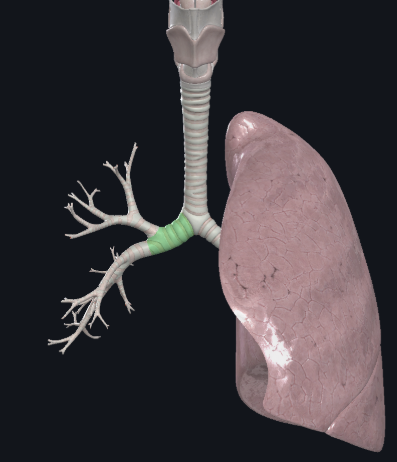

What structure is this?

Right main bronchus

What structure is this?

Right superior lobar bronchus

What structure is this?

Middle Lobar bronchus

What structure is this?

Right inferior lobar bronchus

What structure is this?

The carina